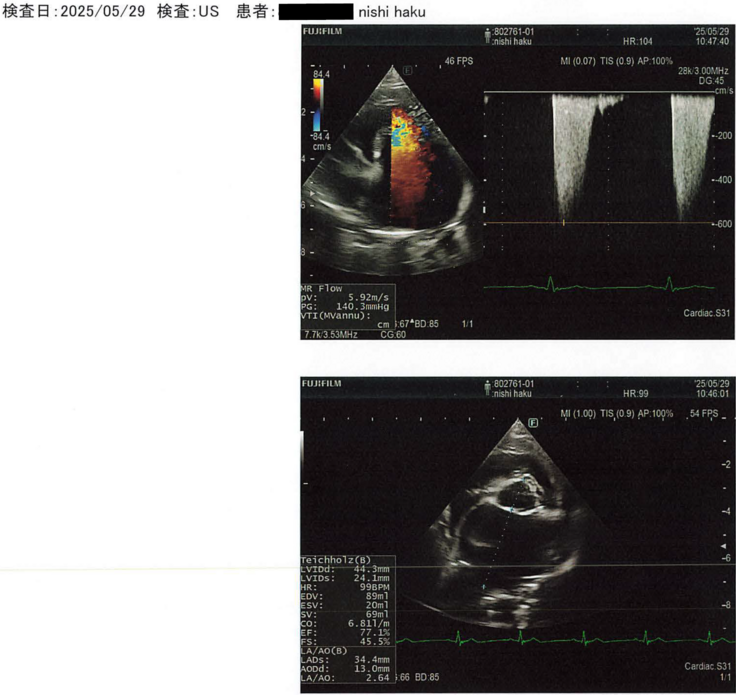

違う病院へ連れていくと、「僧帽弁閉鎖不全症による肺水腫」と診断。心臓の弁がうまく機能せず、血液が逆流し、肺に水が溜まってしまう病気です。以前から時折、唾を吐くような仕草があったのですが、今思えば、あの時から軽度の肺水腫の症状が出ていたのかもしれません。もっと早く気づいてあげられていれば…。「ごめんね、ハク」という後悔の念で胸が張り裂けそうになりました。

「6歳という若さで肺水腫を起こすほど進行しているのは稀なケースです。

このまま内服治療を続けても、心臓や腎臓は長くは耐えられません」と。